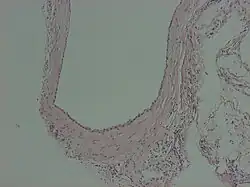

Peritoneal inclusion cyst

A peritoneal inclusion cyst is a cyst-like structure that appears in the pelvis due to non neoplastic reactive mesothelial proliferation, often as a consequence of prior episodes of pelvic inflammation, as can occur in pelvic inflammatory disease. It has the potential to mimic ovarian cysts, hydrosalpinx or even malignancy, due to its nonspecific anechoic appearance.[1]